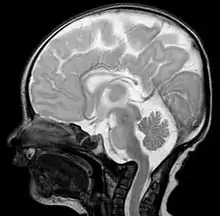

Базилярная инвагинация — деформация основания затылочной кости, сопровождающаяся внедрением костных элементов края затылочного отверстия, мыщелков затылочной кости и зубовидного отростка второго шейного позвонка в полость задней черепной ямки[1].

На рентгенограммах, компьютерных и магнитно-резонансных томограммах зубовидный отросток находится выше линии Чемберлена (линии, которая соединяет задний край твёрдого нёба с краем задней губы большого затылочного отверстия[1].